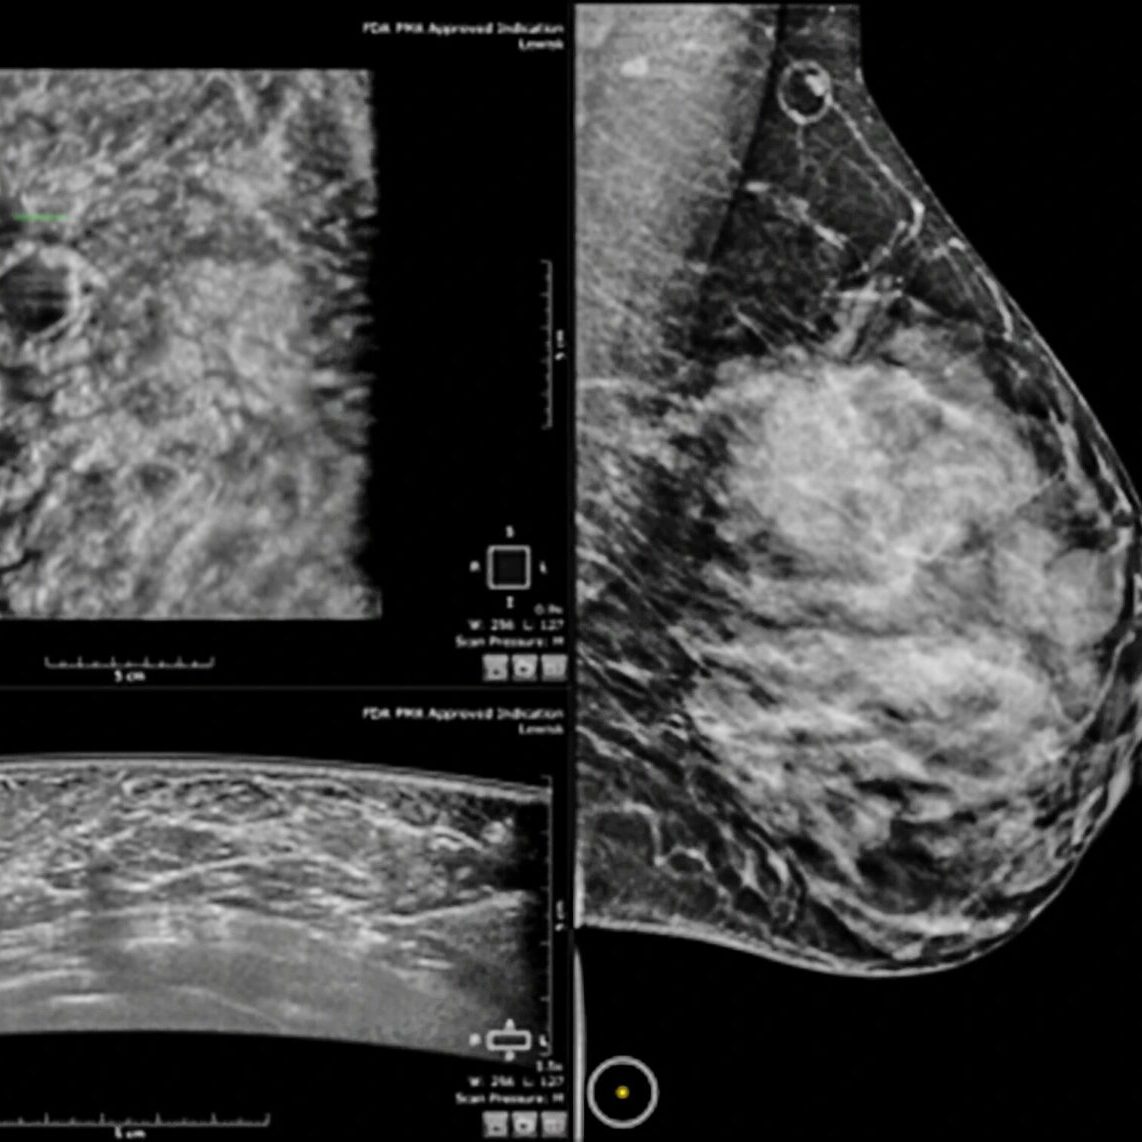

Imaging Associates established the newest Designated Comprehensive Breast Imaging Center in Anchorage, which covers Eagle River, and the only CBIC in the Mat-Su Valley. We provide all breast imaging services: mammography, breast ultrasound, breast biopsy and breast MRI in one location. We offer 3D mammography which is associated with a 40% better cancer detection rate and 15% fewer callbacks and false-positive results.

CBIC is a ‘gold standard’ designation given by the American College of Radiology to sites who meet stringent image quality, safety, and subspecialty criteria.The CBIC accreditation process takes 4 to 6 months and must be renewed every 3 years. Being a CBIC means Imaging Associates is committed to providing Alaska’s women with the most accurate and timely diagnostic care.